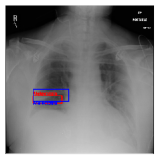

CXR8 [21] is one of the most commonly accessible radio-logical examination for many lung diseases. The data consists of 112,120 images collected by 30,805 patients. As shown in Table I, nine class labels of normal state and eight diseases including cancer are defined for classification. The data is divided into training set and test set, and the classification accuracy and ROC curve with several well-known deep network such as VGG16, GoogLeNet, and ResNet, are reported on the original paper [21]. In addition, 984 Bounding Boxes (B-Box) are provided for localization. Fig. 5 shows image examples of CXR8. The red rectangle in the image shows given B-Box.

Refer to caption

(a) Atelectasis

(b) Mass

Figure 5: Image examples of CXR8